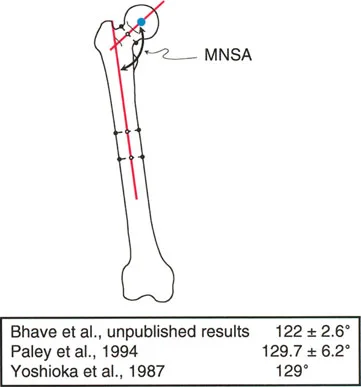

زاوية عنق الفخذ الميكانيكية (MNSA)

تاريخياً، كانت زاوية عنق الفخذ التشريحية هي المستخدمة (عادة 125-131 درجة). ولكن في تصحيح التشوهات، تعتبر زاوية عنق الفخذ الميكانيكية حيوية. وهي الزاوية بين المحور الميكانيكي لعظم الفخذ ومحور عنق الفخذ.